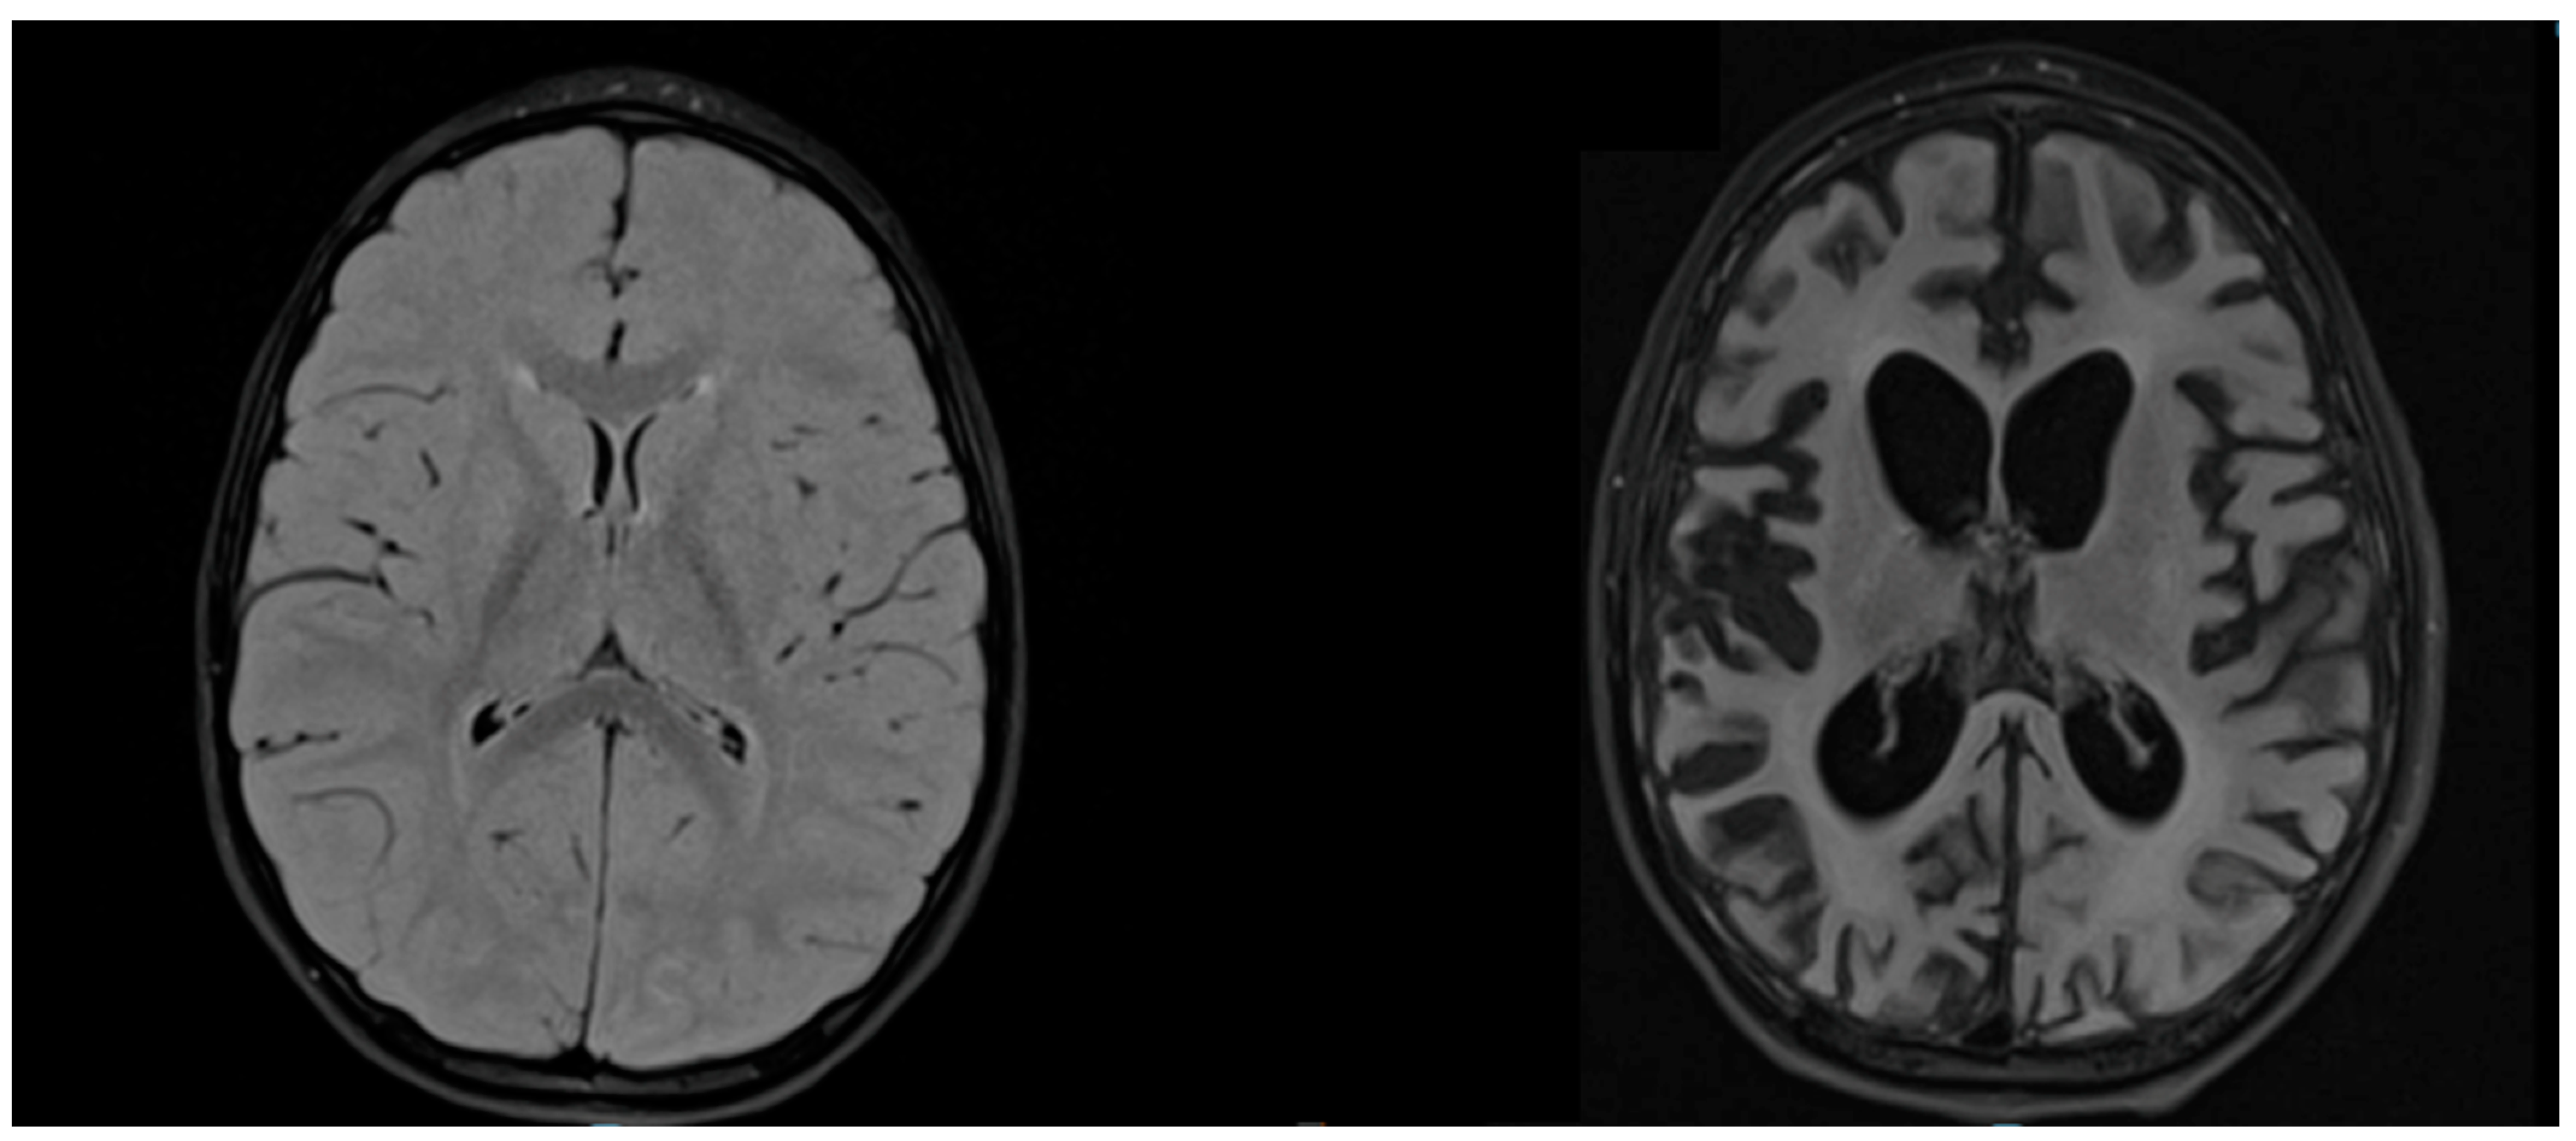

| A | M | 15 days  | Mother | I (1 y); II (6 y) | 3.9 y | Regressive behaviours, massive myoclonus, atonic seizures | 2 A | 29.3 | 0 | 19.9 | 10.78 | Profile type 3 (more than 6 IgG-type bands in CSF)  | Periodic bursts of high-voltage slow waves every 7 s | Frontal and parietal cortical and subcortical regions | Not performed |

| B | M | 3 years  | NA | I (1 y); II (7 y) | 15 y | Focal and atonic seizures, massive myoclonus, cognitive impairment, ballistic movements | 2 C (#) | 29.3 | 3 | 4.66 | 1.32 | Profile type 3 (more than 6 IgG-type bands in CSF)  | Periodic bursts every 11 s with right-sided and temporo-parietal predominance | Centrum semiovale, internal capsule, corona radiata | Not performed |

| C | M | 11 months  | Mother | Not vaccinated | 5.5 y | Cognitive impairment, focal epilepsy,  acute deterioration with spastic tetraparesis, enteral feeding  | 3 | 29.4 | 2 | 21.5 | 7.08 | Profile type 4 | Periodic bursts with right-sided slow diffuse activity | Thalamic, mesencephalic, capsular, corpus callosum regions | Not performed |

| D | M | 14 days  | Mother | I (1.1 y) | 3.9 y | Myoclonus, atonic seizures | 2 B | 23 | 1 | 12.9 | 2.25 | Profile type 3 (at least 3 IgG-type bands in CSF)  | Diffuse periodic bursts of high-voltage slow waves | Bilateral posterior parieto-occipital regions | Not performed |